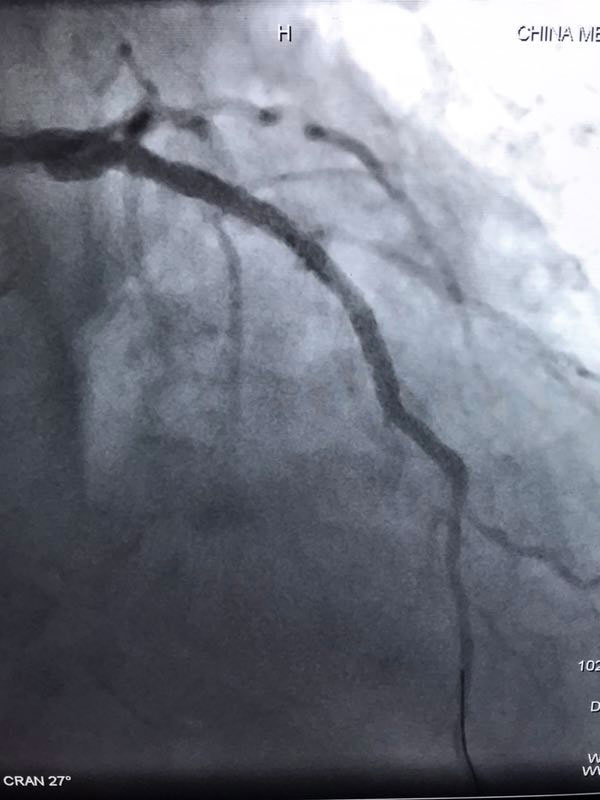

据了解,三位患者都是因严重心绞痛和非ST心梗入院,最高年龄88岁,另两名也有70多岁,是普通PCI难以治疗的危重患者。其中两名已辗转多家医院,均未得到有效救治。患者转入我院后,我院心内科在吴迪主任的带领下,经过周密的准备和科学评估,在血管内超声和临时起搏的辅助指引下,圆满完成了三台旋磨加PCI手术,术后IVUS显示治疗部位支架充分覆盖贴壁,彻底解决了三位患者的病痛,改善了长期预后。

据吴迪主任介绍,冠脉钙化病变和慢性闭塞病变一直是冠心病介入治疗的两大难题,特别是占20%比例的钙化病变,极大的难度风险及高并发症低成功率对心脏介入医生而言是巨大的壁垒和挑战。冠脉旋磨技术作为国家临床二类新技术,就是针对复杂严重钙化病变,通过特制的金刚石探头,在导丝指引氮气加压推进下送入冠脉,借助每秒高达17万转的高速旋转将钙化部位磨平断开,然后借助切割球囊分解斑块,为最终顺利植入支架创造条件。